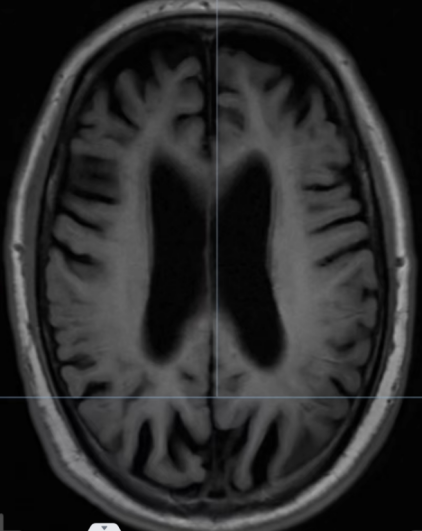

张伯的颅脑核磁平扫表现出了与之年龄很不匹配的脑萎缩,尤其是在弥散成像上呈现出脑梗死的高信号表现。

不同于脑梗死,张伯的弥散成像高信号改变有特征性——是分布于额顶叶皮层与白质交界区线样高信号。